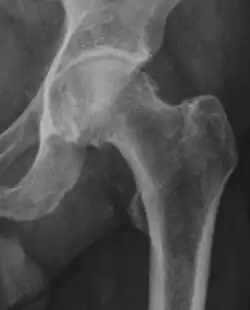

Radiograph of a pincer type impingement.

Projectional radiography ("X-ray") is often considered first line for FAI.[10] Anterior-posterior pelvis and a lateral image of the hip in question should be attained.[10] A 45-degree Dunn view is also recommended.[10][19]